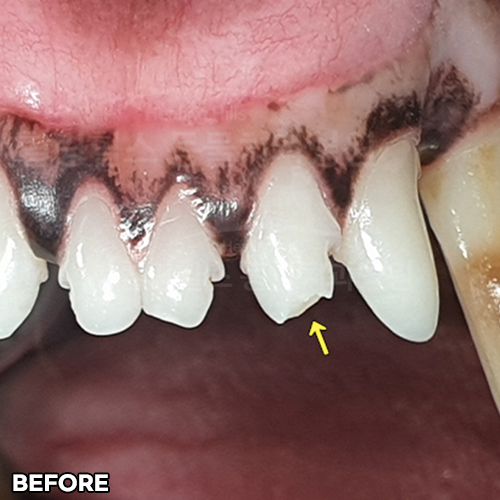

최고 난이도 강아지신경치료 - 꽉막힌 근관&치수괴사! 커다란 반려견치근단농양! 녹아내린 턱뼈! 치통으로 사나워진 모습! 강아지 신경치료 & 치주치료 한달 뒤 좋아졌어요!